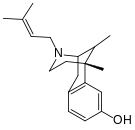

There are a number of broad classes of opioids:[260]

- Fully synthetic opioids: such as fentanyl, pethidine, levorphanol, methadone, tramadol, tapentadol, and dextropropoxyphene;

Morphinan derivatives

- Butorphanol—agonist/antagonist

- Nalbuphine—agonist/antagonist

- Levorphanol

- Levomethorphan

- Racemethorphan